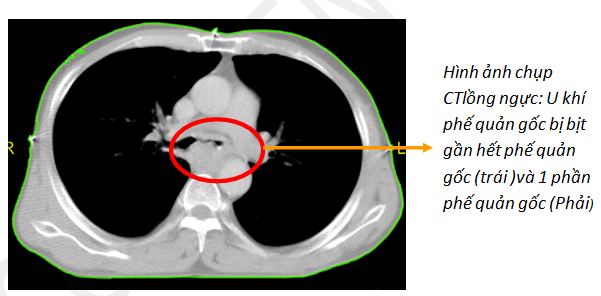

Tiền sử: 2 tháng trước: ho, khó thở . Bệnh nhân được chuyến đến khoa Hô hấp BV Bạch Mai và được chẩn đoán là ung thư khí phế quản . Xếp loại giai đoạn: T4NoMo.

Chẩn đoán mô bệnh học là: Carcinome vảy .

Bệnh nhân không có chỉ định đặt Stent (vị trí chạc 3).

Sau đó bệnh nhân được chuyển đến Trung tâm Y học hạt nhân và Ung bướu bệnh viện Bạch Mai.Sau 2 ngày, tình trạng bệnh cải thiện ít, vẫn khó thở, chỉ nằm được khoảng 10 phút.Bệnh nhân đã được hội chẩn xét đặt stent khí phế quản nhưng khó có thể tiến hành do khối u ở vị trí chạc 3 khí phế quản.

Trước tình trạng bệnh nhân ngày một nặng lên và xấu đi, và có nguy cơ khối u chèn ép vào đường thở gây nguy hiểm đến tính mạng.Nên chúng tôi đã giải thích cho gia đình bệnh nhân: là không còn chỉ định phẫu thuật. Chỉ có thể xạ trị cấp cứu.Đây là phương pháp duy nhất tại thời điểm này.Nếu chậm trễ bệnh nhân chắc chắn tử vong. Tuy nhiên nếu tiến hành xạ trị cấp cứu có thể đem lại cơ hội sống sót cho bệnh nhân nhưng cũng có thể tử vong trong hoặc sau quá trình xạ trị.